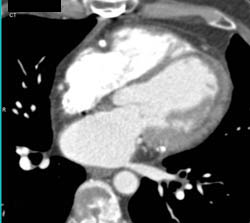

Partially Calcified Aortic Valve